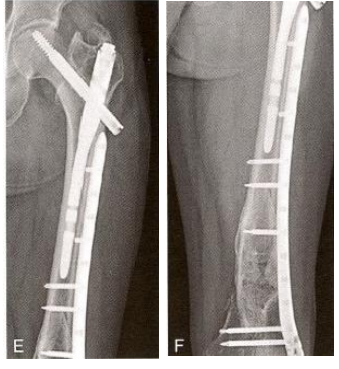

股骨颈合并股骨干骨折(Lambiris I型)(图12-15A) 。 倒打髓内钉 固定股骨干,用多根钉固定股骨颈(图12-15B)。组合式固定与单一髓内钉固定的力学稳定相似,但手术难度低。

图12-15 髓内钉+空心螺钉。A.股骨干合并股骨颈骨折;B.股骨颈骨折,用3枚空 心螺钉固定;C.股骨干骨折、逆行髓内钉固定